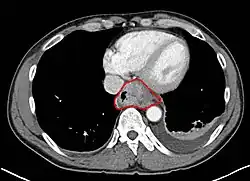

- Lower thoracic esophagus and EG junction:

- Inferior pulmonary veins to the stomach; includes the intraabdominal portion of the esophagus

- By endoscopy, 30 to 40 cm